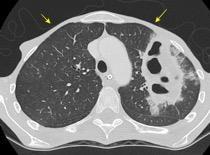

Derrame pleural..33,3% Derrame bilateral.26,7% Ganglios mediastínicos e hiliares..66,7%..

No hiliares

Okada F et al. Chest HRCT findings in acute transformation of adult T-cell lymphoma/leukemia. Eur Radiol 2015

Vidrio deslustrado 60%. Consolidación 33,3% Nódulos…33,3%